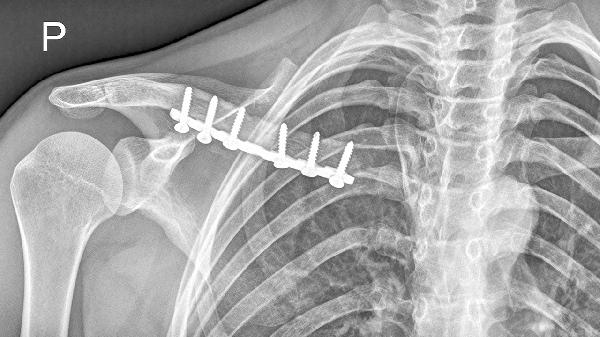

5、锁骨骨折

外伤后出现的剧烈疼痛、肿胀需警惕骨折可能。X线检查可明确诊断,不完全骨折可用锁骨固定带制动,完全移位骨折需手术内固定。恢复期遵医嘱使用接骨七厘片、伤科接骨片等药物,配合红外线照射促进骨痂形成。